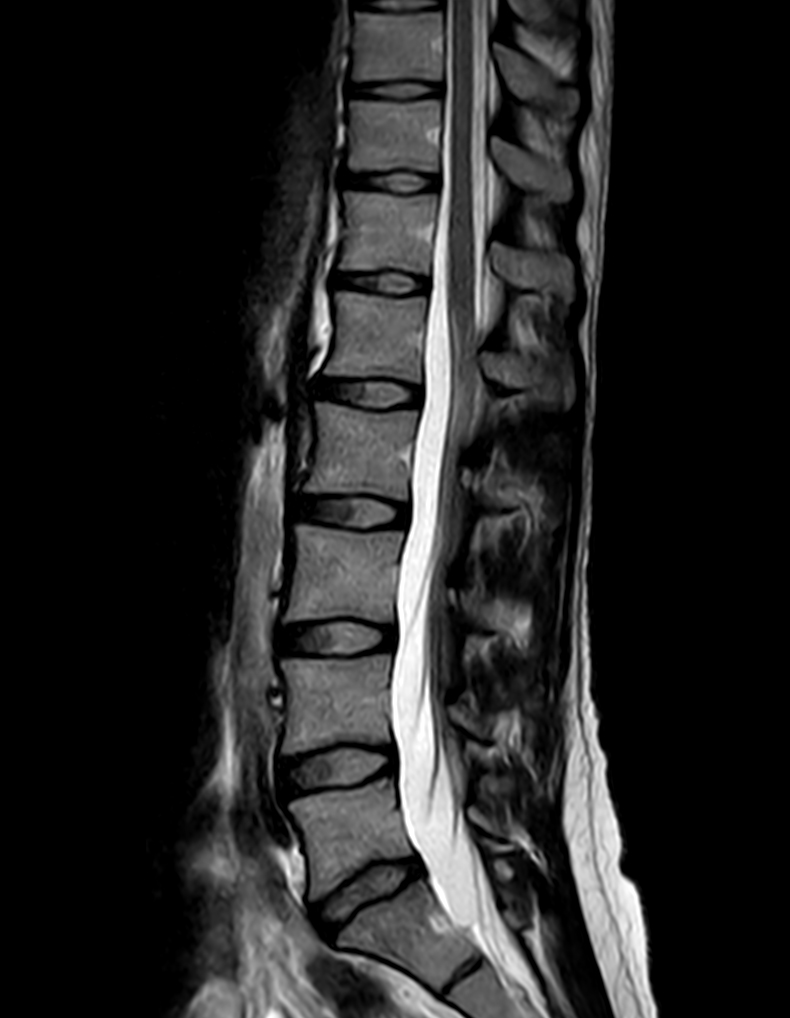

Sagittal T2w TSE